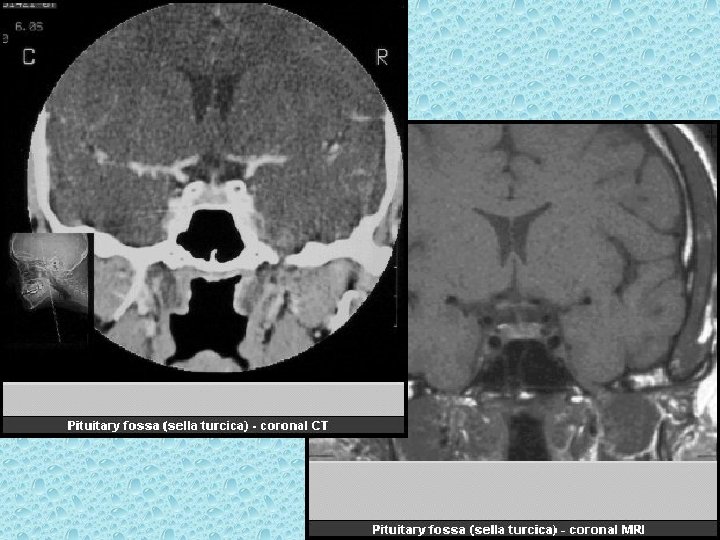

SELLA TURSİKA • • • Sfenoid kemik korpusundadır Anterior ve posterior clinoidler Hipofiz fossası Dorsum sella İçerisinde hipofiz bezi bulunur